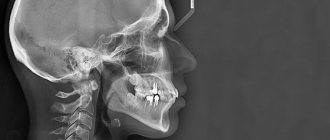

Приступаем к постоянному протезированию металлокерамикой

На снимке вы видите цельнофрезерованный каркас из кобальт хрома. На фото — основа будущего металлокерамического протеза. По полученным слепкам техник выполнил модель, виртуально смоделировал каркас для будущих постоянных керамических коронок. После этого фрезеровальный станок выточил целую дугу, которую мы должны примерить пациентке.

Теперь, если все подходит, все параметры дуги протеза отвечают поставленным задачам, то техник приступает к облицовке этой дуги керамикой нужного цвета и нужной формы. Так зарождается эстетика протезирования.